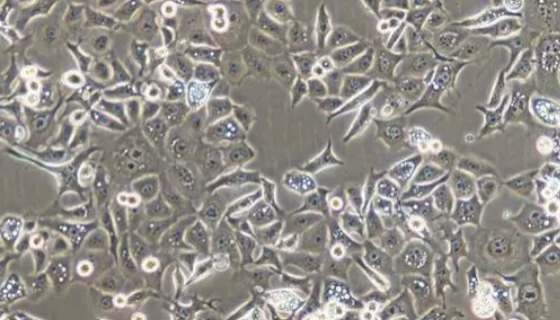

人胰腺癌細(xì)胞的培養(yǎng)操作與應(yīng)用及研究動(dòng)態(tài)!

人胰腺癌細(xì)胞可以用于SPINK1慢病毒過(guò)表達(dá)載體和其穩(wěn)轉(zhuǎn)As...